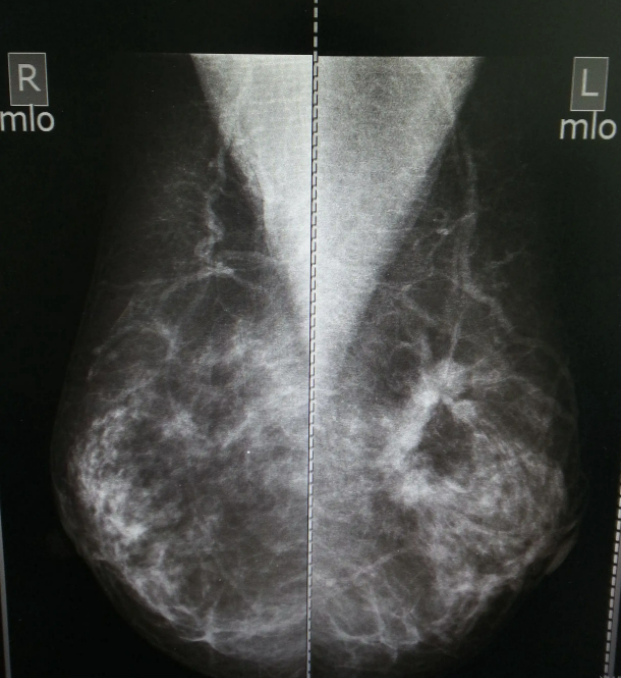

鉬靶照相是利用軟X線對乳腺組織進行攝像,通俗地說,就是乳腺的“夾板拍片”,是將乳腺放置于兩塊特制平板中,壓緊后進行攝片,以達到對乳腺內(nèi)組織進行診斷的目的。

依據(jù)病變與正常乳腺組織間的密度差,鉬靶攝影下乳腺癌的表現(xiàn)為腫塊結(jié)節(jié)影和鈣化灶。細沙樣、蠕蟲形、成簇形的鈣化影也是早期乳腺癌特征性的表現(xiàn),這樣的檢查有利于早期發(fā)現(xiàn)乳腺癌。

2、常規(guī)檢查需要拍攝四張照片,分別是雙側(cè)軸位及雙側(cè)側(cè)位或斜位。

02 鉬靶影像中,乳腺癌是什么樣子?

乳腺癌腫瘤生長較快,內(nèi)部常出現(xiàn)壞死、鈣化,這些癥狀容易被鉬靶檢測到。

乳腺癌的鈣化經(jīng)常表現(xiàn)為細小泥沙樣鈣化,這種鈣化很密集,呈一簇一簇的,粗細不均,濃淡不一。鈣化可能在腫塊內(nèi),也可能在腫塊外,也可能看不到腫塊,只看到鈣化。

部分惡性腫瘤,鉬靶影像僅表現(xiàn)為單純腫塊,典型的乳腺癌表現(xiàn)為圓形或類圓形,可能有分葉狀、毛刺狀或觸角狀。